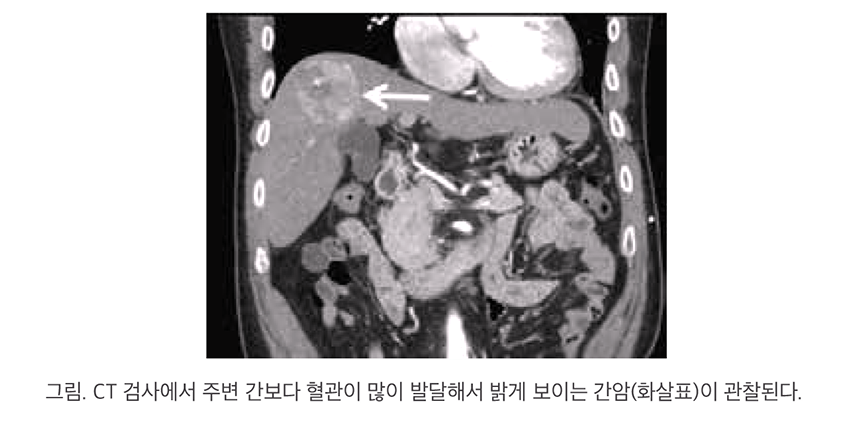

최근 대한간암학회에 따르면, MASLD 환자는 간암 발생률이 일반인보다 10배 이상 높은 것으로 나타났습니다. 더 충격적인 점은 MASLD 관련 간암이 간경변 없이도 발생할 수 있다는 사실입니다. 이는 MASLD가 조기 증상이 거의 없고 간에 서서히 염증과 손상을 일으키기 때문입니다.